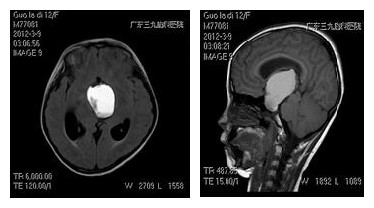

患儿,女,12岁,因“发作性头痛1年余,加重伴视物模糊1月”入院。患儿视力:右侧眼前1米指数,左侧0.3。行头颅CT检查提示:鞍区巨大占位性病变合并梗阻性脑积水。

术前